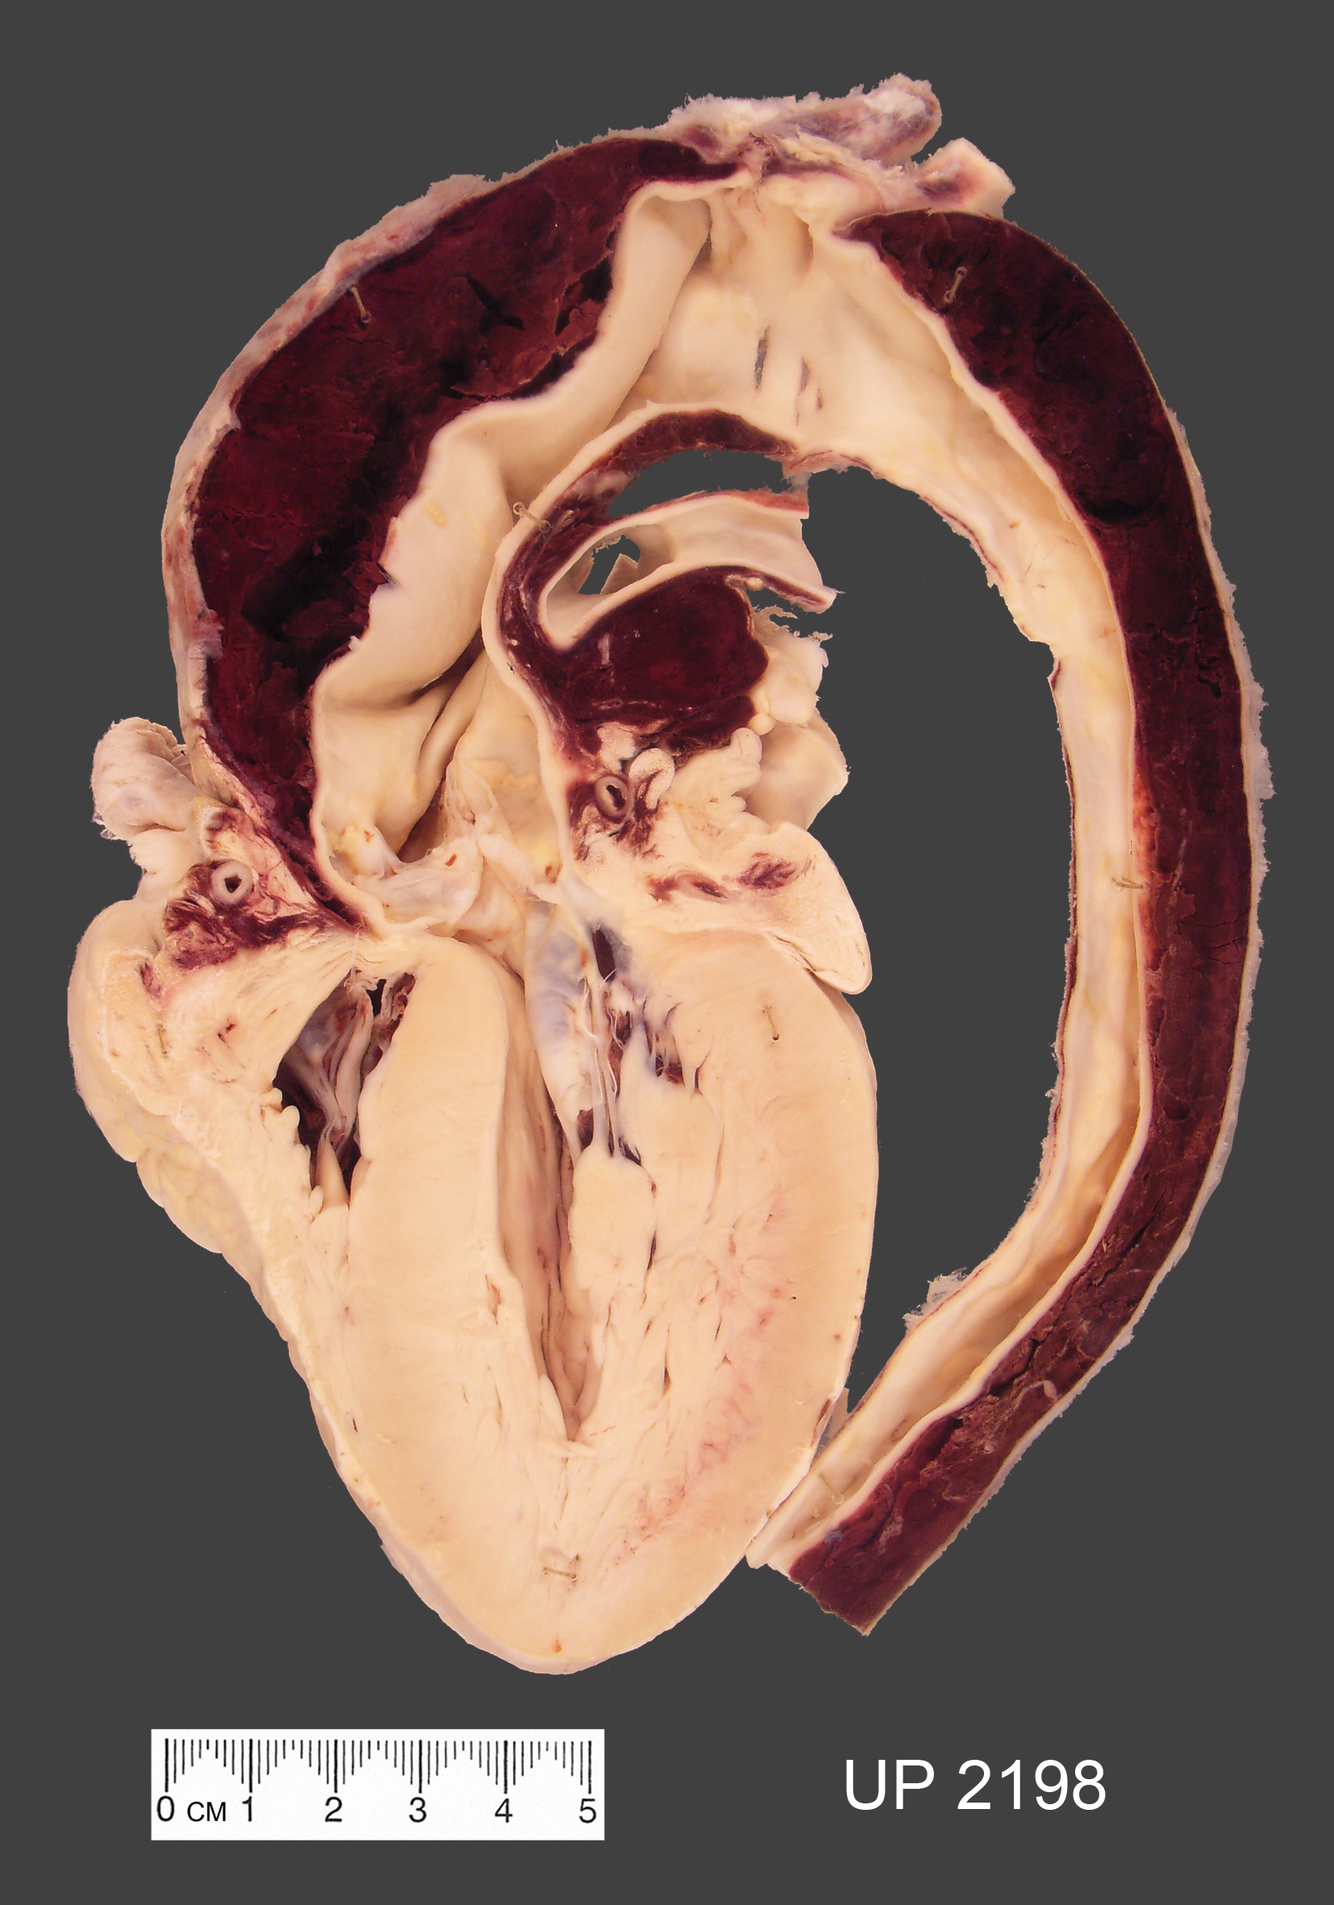

The mounted specimen shows the heart and thoracic aorta.

There are two transverse tears in the arch of the aorta. These represent the origin of the dissecting aneurysm. The blood has dissected the outer media and adventitia from the inner media creating a false channel within the wall of the aorta. The dissection has extended proximally to the root of the aorta resulting in a haemopericardium (the blood in the pericardial sac has been washed from the specimen) and the dissection has extended distally involving the entire thoracic aorta.

Dissection typically occurs in older patients, usually men, with hypertension and in younger patients with connective tissue defects eg Marfan’s syndrome. The common factor is degeneration of the media of the vessel wall. with loss of normal extra-cellular matrix synthesis and an increase in amorphous ground substance, cystic medial degeneration.